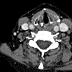

Axial contrast-enhanced neck CT (10 days after FDG-PET) shows a borderline enlarged level III lymph node (orange arrow) at the level of the lower border of the left supraglottic mass. There are no other enlarged cervical lymph nodes outside this region.